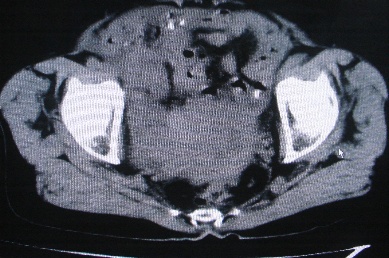

以下是引用卜一在2007-4-30 15:29:00的发言:[br]子宫明显增大,不规则,子宫壁不规则增厚,子宫腔明显缩小,子宫右侧软组织团块与子宫关系密切,内见低密度坏死区。考虑:子宫癌并周围侵润。